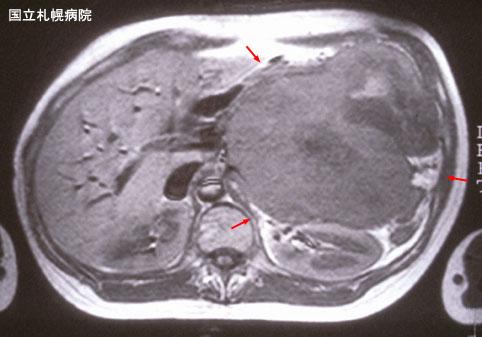

위압배 소견이 강하게 나타난 거대한 복강내골외성 Mesenchymal chondrosarcoma.(증례제시:국립 삿포로병원)

[Image-ID:3271]

MRI

종양의 최대경(밀리미터)

40이상